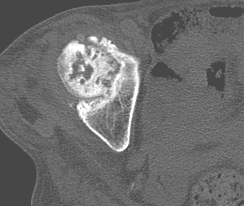

以下是引用老爱克斯新网客在2009-2-3 19:42:00的发言:[br]右侧髋臼及右侧股骨头可见明显骨质破坏,以溶骨性破坏为主,无明显硬化,髋关节间隙变窄,周围软组织明显肿胀,密度不均,脂肪间隙消失。[br] 诊断:右侧髋关节感染性病变,右侧髋关节结核的可能大。[br] 鉴别诊断:1.股骨头缺血坏死,单纯股骨头缺血坏死病例不会累积髋臼骨破坏。2。退行性关节炎,以骨质增生为主,伴有关节面硬化,骨质破坏呈多发小囊状破坏为主,其周围可见硬化环。3.股骨头缺血坏死晚期(第四期)骨质破坏可伴髋关节退行性变,可有骨质增生,但此时骨破坏以股骨头破坏为主,不应该伴有髋臼骨质破坏,因为股骨头的骨破坏是因血运中断,而没有髋臼的血运中断,又没有细菌的感染,怎么能造成髋臼的骨破坏呢。